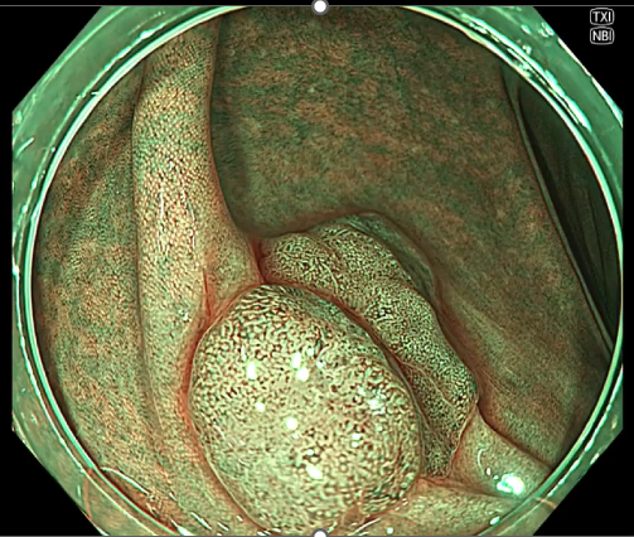

大腸腺腫の画像

NBI(左)よりNBI+TXI(右)では表面構造や血管の視認性が向上している。